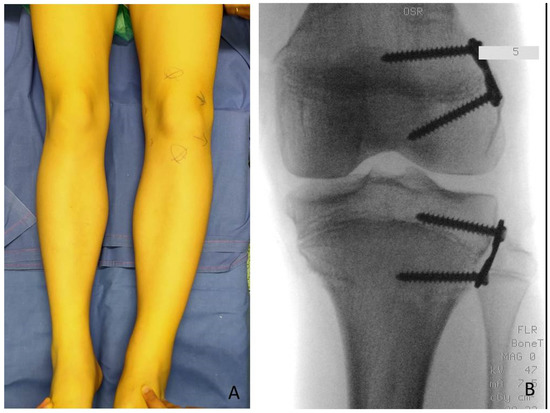

In one case of a girl who had 3.5 cm of LLD at the age of 9 years, a DFE was performed as the first procedure and PTE as the second procedure because of the low growth potential. After successful correction all implants were removed in a third procedure after 2.5 years. In one case of a boy with 10 cm of LLD at the age of 2.11 years TE with PTE and DFE was performed in one step despite the young age (Figure 7).

Figure 7. BWS male child with LO (lateralized overgrowth) right and severe LLD (leg length discrepancy): (A) clinical aspect showing both femur and tibia length discrepancy; (B) femur and tibia length discrepancy is clearly visible from lateral with flexed hips and knees; (C) LLD of 10 cm is present; (D,E) PTE (temporary proximal tibia epiphysiodesis) and DFE (distal femur epiphysiodesis) were performed in one step at same time at age of 2.11 years, X-ray in antero-posterior projection showing position of guided growth system with 8-plates straddles distal femoral physis and proximal tibial physis.